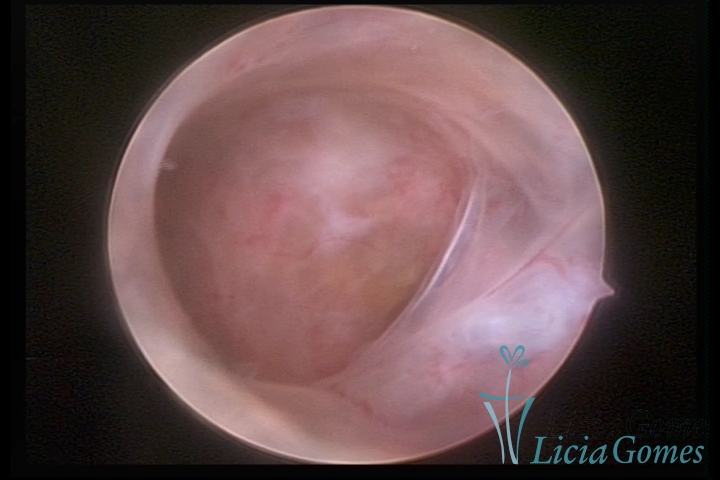

SINÉQUIA TIPO MUCOSA